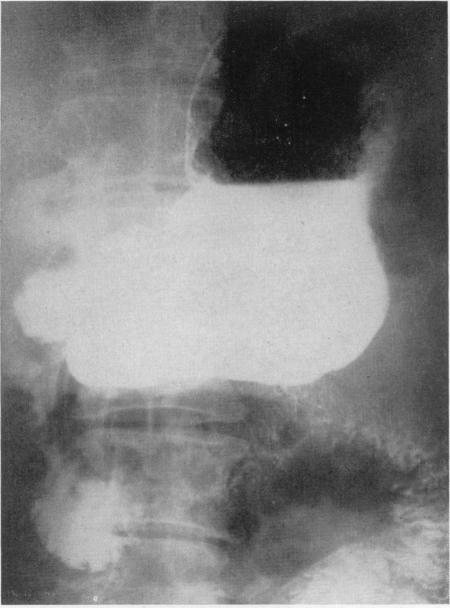

Tumours of the stomach other than carcinoma.

Ann R Coll Surg Engl. 1956 Apr;18(4):228-45.